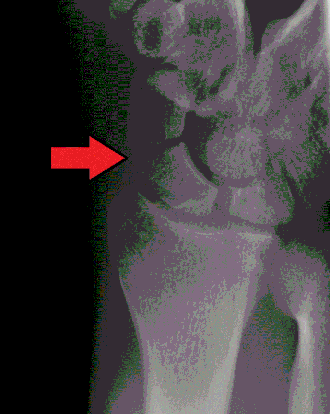

Raio-X de uma fratura do escafoide